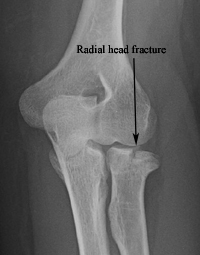

What are radial head/neck fractures?